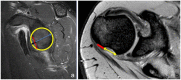

Results: The incidence of anterior shoulder instability events in the military occurs at an order of magnitude greater than in civilian populations, with rates as high as 3% per year among high-risk groups. With more than 90% risk of a Bankart lesion and high risk for instability recurrence, the military has advocated for early intervention of first-time shoulder instability while documenting up to 76% relative risk reduction versus nonoperative treatment. Preoperative evaluation with advanced radiographic imaging should be used to evaluate for attritional bone loss or "off-track" engaging defects to guide comprehensive surgical management. With complex recurrent shoulder instability and/or cases of clinically significant osseous lesions, potential options such as remplissage, anterior open capsular procedures, or bone augmentation procedures may be preferentially considered.